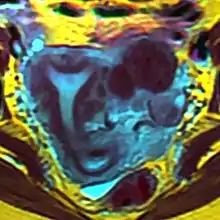

| Arcuate uterus (marked in red) seen on MRI | |